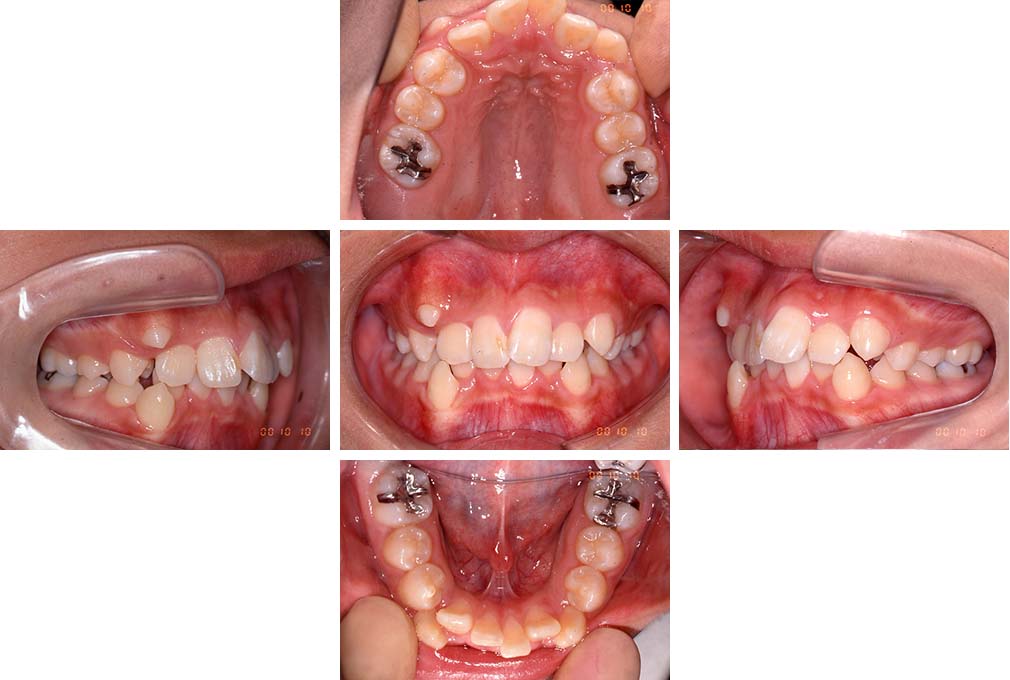

CASE:01

叢生を伴う骨格性上顎前突

初診時年齢 15歳10カ月

性別 男性

治療費の目安 約75万円程度(治療開始時)

上顎前歯の前突と叢生を主訴として来院された。大臼歯関係は左右側ともにⅡ級で上顎の方が前方に位置していた。叢生を伴う骨格性上顎前突と診断し、上下顎小臼歯抜歯を行っていただきマルチブラケット装置に顎外固定装置を併用して動的治療を行った。顎外固定装置や矯正用ゴムの使用など協力状態も良好で、動的治療期間2年0カ月、調整来院20回でマルチブラケット装置を撤去し保定へ移行した。動的治療終了後10年0カ月を経過したが保定移行時とほぼ同様の咬合状態で良好な状態を保っていた。

治療前

15歳10か月

治療後

動的治療期間2年0カ月

18歳5か月

10年経過

動的治療終了後10年0カ月

28歳5か月